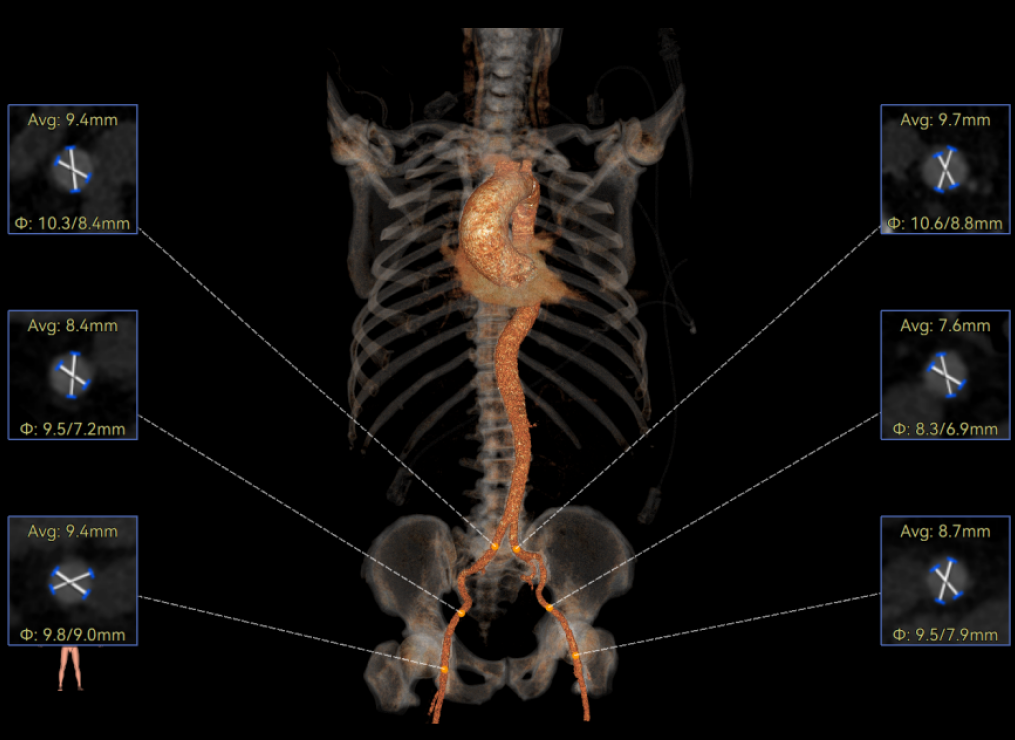

病例概览

患者病史 男性,74y, 因 “发现心脏瓣膜病 1 年,加重伴喘气半年” 入院。门诊检查显示主动脉瓣重度AS并伴轻-中度AR。患者基础疾病较多:胸腹主动脉多发穿透性溃疡、心功能III级等,手术指征明确,但风险极高。 术前CT LVOT- Annulus 倒梯形,对植入瓣膜有挤压位移风险,Annulus直径23.7mm,瓣叶增厚,钙化集中在无冠窦边缘。 左冠脉开口高度可,瓣叶不长、窦部空间较大,无冠脉风险;室间隔膜部较短,有一定PPI风险,心脏角度37.9°;心室较小,有一定循环崩溃风险,术前注意补液。 术前造影角度及入路:血管入路散在钙化、无迂曲;主动脉弓条件好、双侧股动脉直径大、右股穿刺点侧壁存在环形钙化 左右重合位:RAO 7° CAU 21° 右窦中心位:LAO2 1° CAU 1° 手术策略 20mm球囊预扩后植入AV26瓣膜,同时做好预防循环崩溃、传导阻滞的应急预案。 术中挑战 1)球囊预扩:20mm球囊预扩时无明显 “腰征”,但存在少量反流,提示瓣膜钙化与解剖结构对扩张的阻力不均 2)首次释放偏差:第一次定位释放时,瓣膜在 “开花” 过程中下滑约 3mm,工作位观察显示小弯侧瓣周漏较多(深度超过完全覆膜区),需二次调整。 3)二次精准定位:以猪尾导管为参照,将定位点调整至 “猪尾 - 2mm” 处,结合真实窦底深度(较深)重新释放,最终瓣膜位置稳定,瓣周漏显著减少。 术后即刻效果: 瓣膜形态良好,跨瓣压差从术前的 67mmHg 降至 6mmHg,且无明显瓣周漏,冠脉开口通畅; Commisural Alignment 术后即刻超声: Prostyle A®预装干瓣——助力临床最优化解决方案: √ 平衡的径向支撑力:特殊的解剖结构下位置形态良好,术后跨瓣压差大幅降低,血流动力学改善明显; √ 80%可回收设计:支持术中二次调整释放位置,保证精准释放; √ 平衡的收腰设计&Commissural Alignment设计: 为患者后期冠脉PCI保留了生命通道;